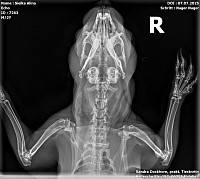

Röntgenbilder

Interressant, oder? Troll sein gebrochener Zeh und Echo seine Kniefraktionen und sein Stufengebiss.

Echo bekommt ein vorbeugenes Mittel gegen Arthrose und kriegt einen Zahnarztbesuch (Leipzig) und Troll wird jetzt bei Dr. Rust im Salzatal vorgestellt.